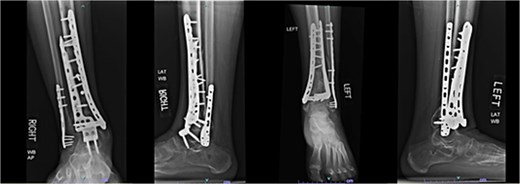

A 38-year-old male with a BMI of 27.5 kg/m2 and a history of alcohol use disorder, paranoid schizophrenia, smoking, and prior bilateral calcaneal fractures treated with ORIF 4 years earlier sustained bilateral pilon fractures after jumping from a third-story window (Fig. 3). He presented to the hospital 5 days after injury.

AP and oblique radiographs of patient 2 obtained after a fall, demonstrating bilateral pilon fractures and retained hardware from prior bilateral calcaneal ORIF.

Initial surgery occurred 3 days after presenting to the hospital and involved definitive ORIF of the left leg using a distal tibial locking plate and a distal fibular locking plate. At the time of the initial surgery, there were significant fracture blisters that prevented definitive fixation of the right leg; thus, an external fixator was applied to the right leg. One week later, ORIF of the right leg was performed with distal tibial and fibular locking plates. The patient was made NWB bilaterally and required a wheelchair for mobility during the first 12 weeks. Although he was instructed to use crutches once partial weightbearing (PWB) was permitted, he demonstrated poor adherence to these restrictions.